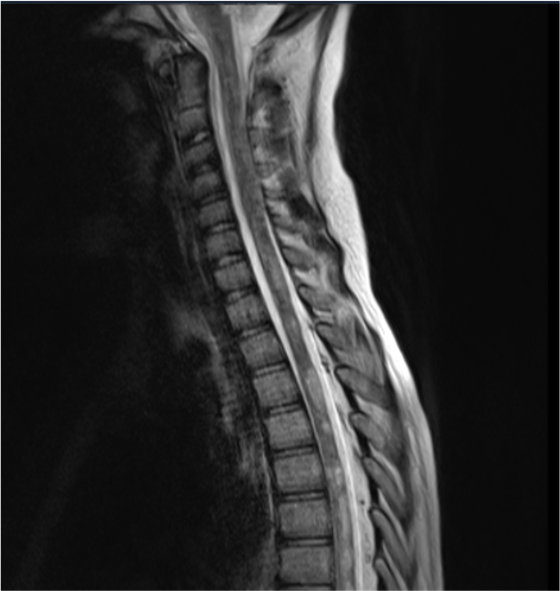

Veniva quindi sottoposta a risonanza magnetica di encefalo e midollo con riscontro di plurime lesioni encefaliche, sia sovra che sottotentoriali, iperintense in FLAIR e con restrizione in DWI, oltre a lesioni iperintense in T2 nel midollo, sia cervicale che dorsale, tutte con sincrona presa di contrasto (Figura 1). Tali reperti radiologici risultavano compatibili con encefalomielite acuta disseminata (ADEM). Successivamente, veniva effettuata una rachicentesi con prelievo di liquor che documentava iper-proteinorrachia, pleiocitosi cellulare, glicemia nella norma e presenza di bande oligoclonali. Gli esami colturali, citologici, microbiologici e il film-array screening delle meningoencefaliti effettuati su liquor risultavano negativi. A completamento diagnostico, venivano effettuati anche degli esami sierologici che evidenziavano una dubbia pregressa esposizione della bambina all’EBV e una franca positività delle Trimeric IgG anti SARS-CoV-2, mentre le sierologie per gli altri microrganismi risultavano negative.

Dopo tre mesi dall’esordio di tale sintomatologia è stata effettuata una RM che ha documentato una notevole riduzione di enhancement dopo mezzo di contrasto delle lesioni della sostanza bianca biemisferica sovra e sotto-tentoriali e del midollo spinale.